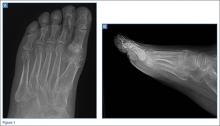

A 55-year-old man presented with a 2-day history of acute first toe pain in his right foot after banging the affected toe on a door. Physical examination demonstrated a swollen first toe with marked tenderness to palpation. Radiographs were obtained (Figures 1a and 1b).

The radiographs of the right foot excluded fracture as the underlying etiology of the patient’s pain. The findings included soft tissue swelling and periarticular (ie, near but not involving the joint) erosions involving the first metatarsal head (white asterisks, Figure 1c). The erosion on the medial aspect of the metatarsal head had remodeling of bone at the periphery of the erosion, which created the appearance of “overhanging edges” (white arrows, Figure 1c). The radiographic appearance suggests the diagnosis of gouty arthritis.